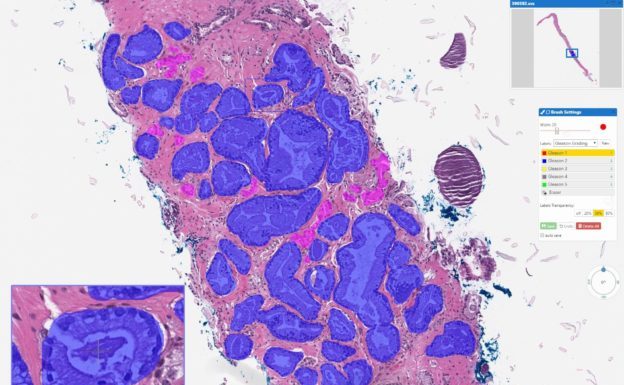

癌症診斷技術研發商 Paige 宣布完成新一輪 4,500 萬美元融資,利用與治療和基因組學相關的資料集來訓練公司的深度學習網路偵測乳腺癌、前列腺癌和其他主要癌症。